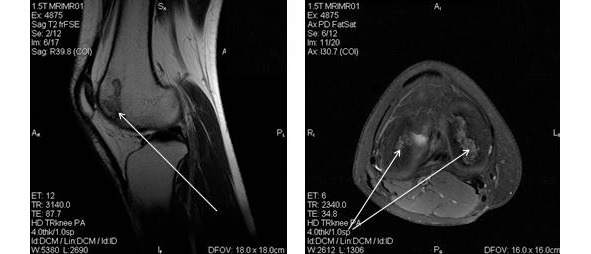

При длительном течение заболевания в связи со снижением физиологической амплитуды движений в коленном суставе развивается атрофия четырехглавой мышцы бедра, что приводит к прогрессированию ортопедических проблем. Среди методов диагностики приоритетное значение имеют методы лучевой диагностики – рентген и магнитно-резонансная томография (МРТ) (рис. 25).

Рисунок 25. МР-картина структурных изменений мыщелка правой и левой бедренной кости, обусловленных инфарктом костного мозга при болезни Кенига